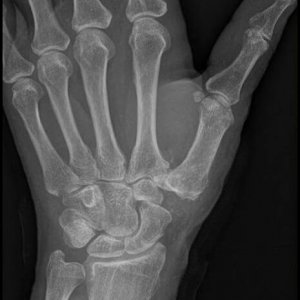

Rhizarthrose Daumensattelgelenk, der Mittelhandknochen des Daumens drückt auf den benachbarten Knochen der Handwurzel, der Gelenkspalt zwischen den Knochen ist deutlich vermindert bzw. aufgehoben.